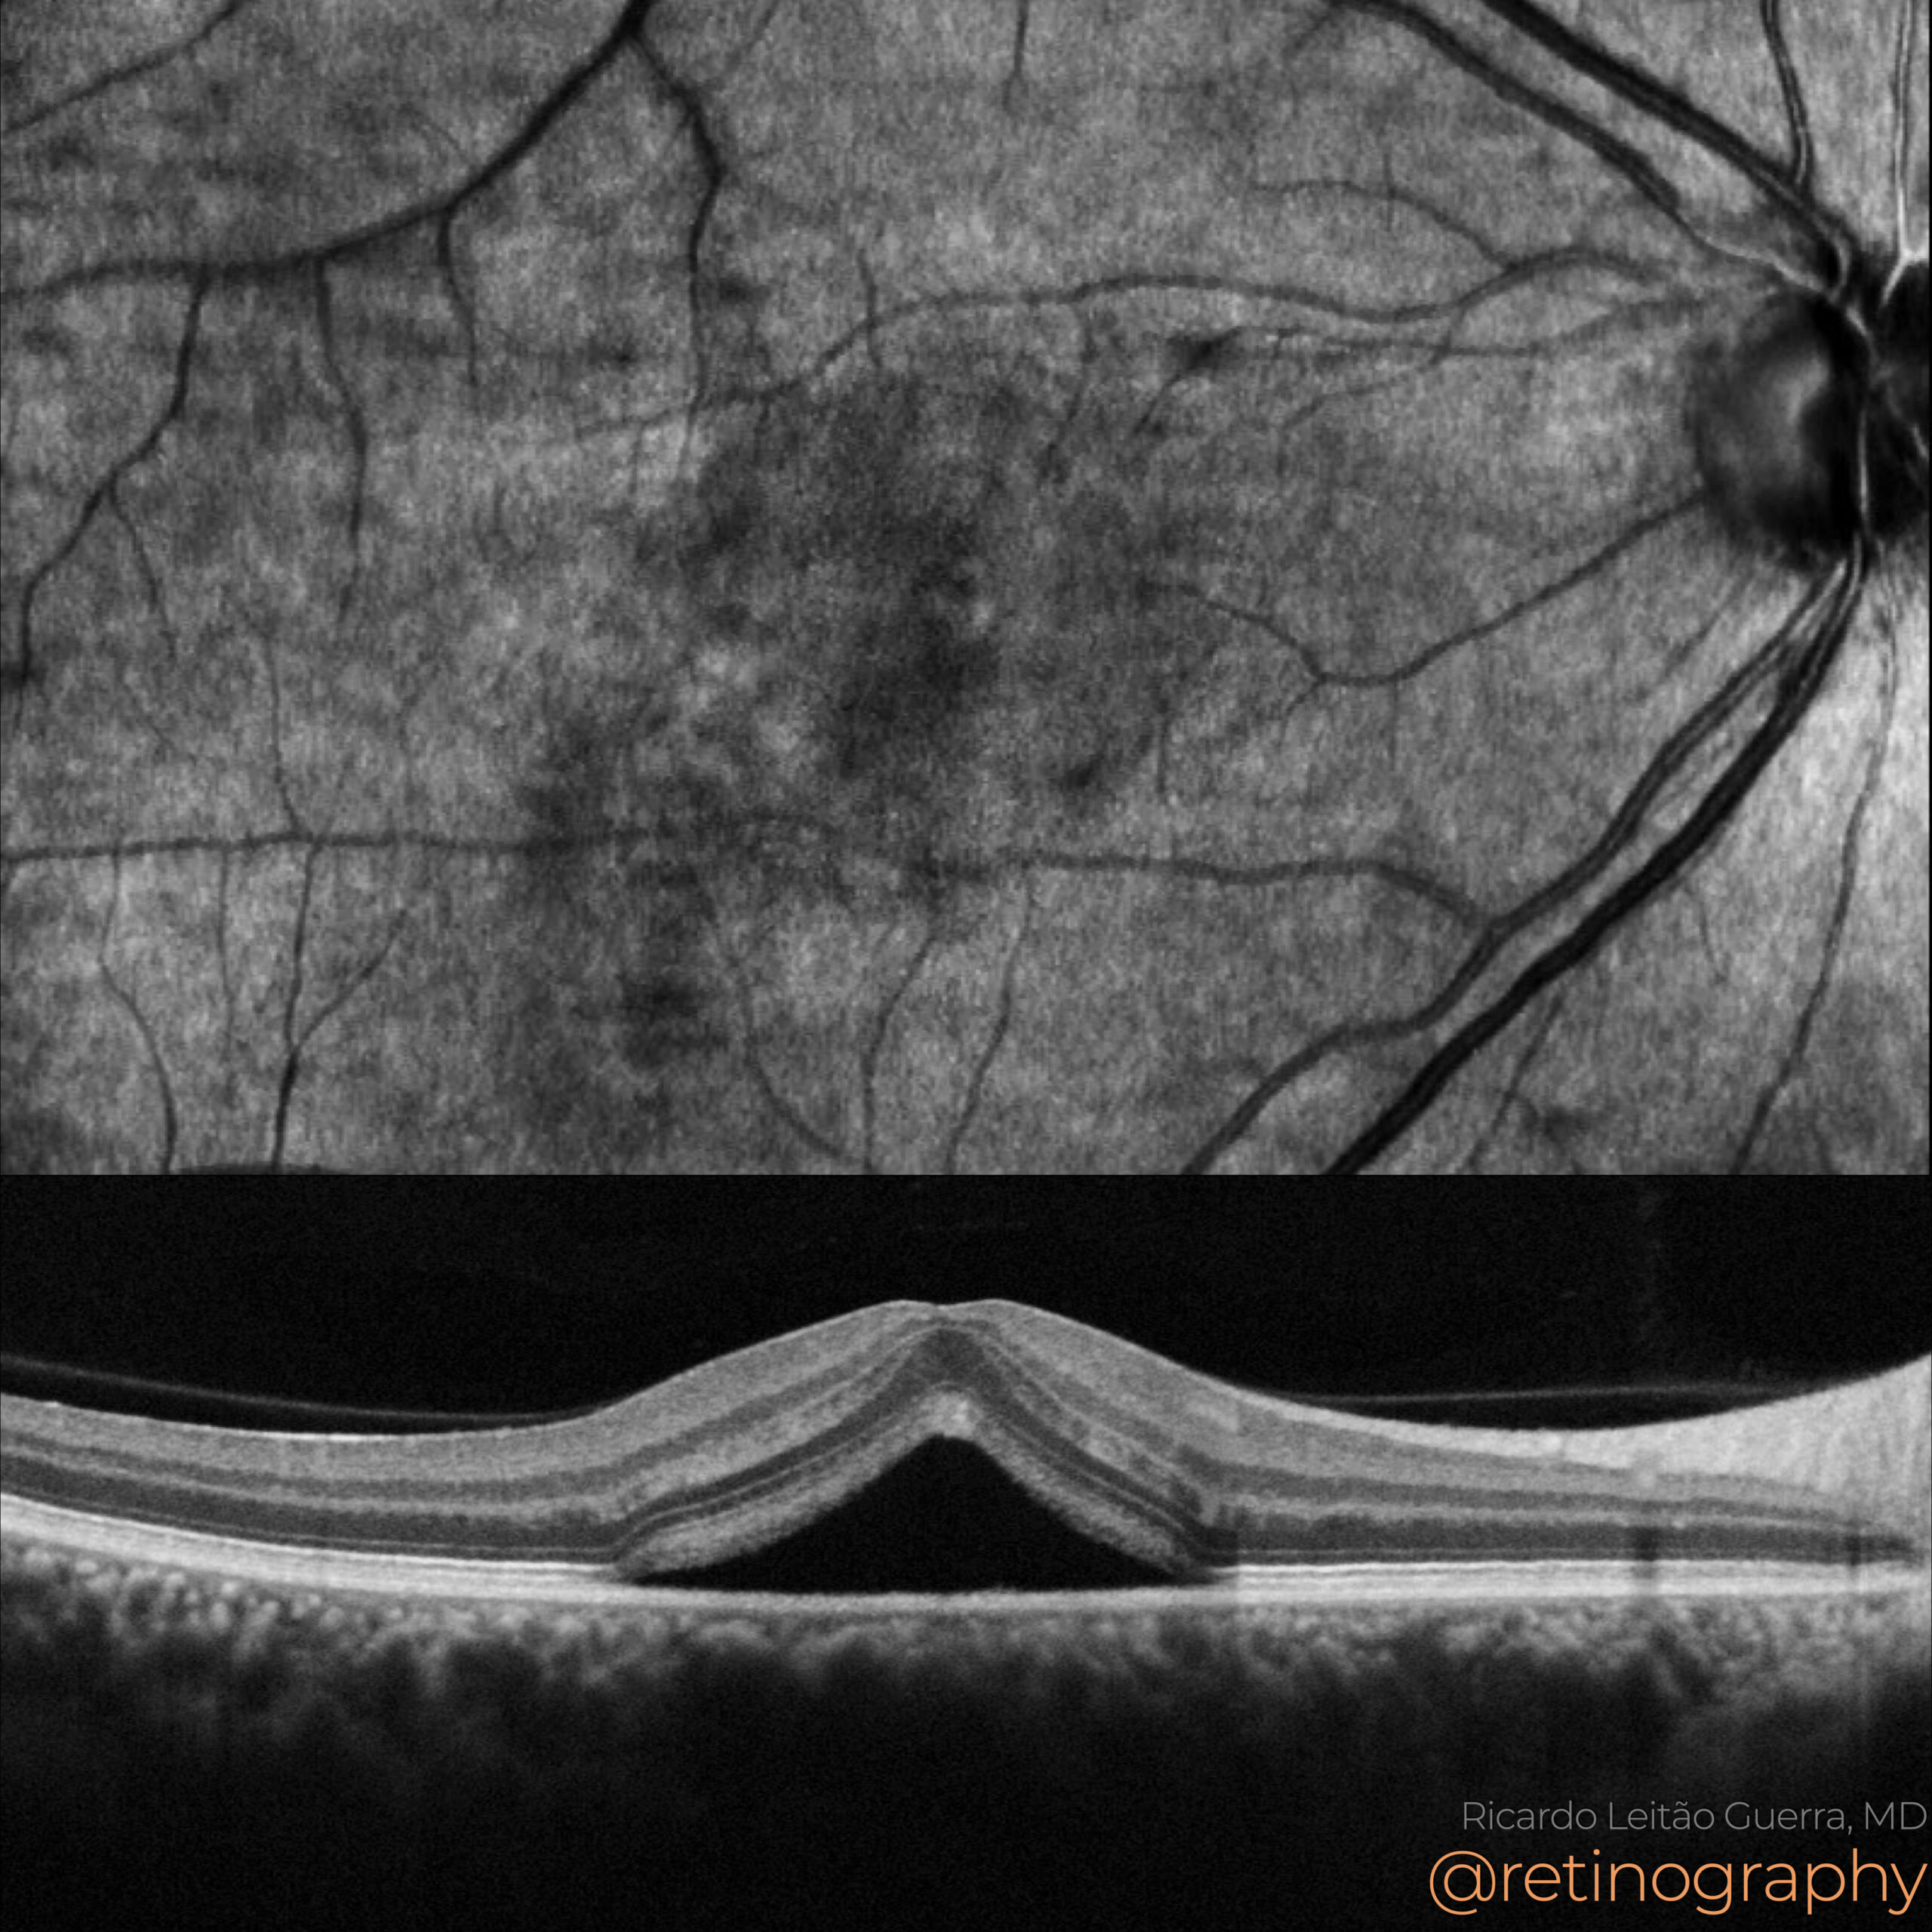

Central Serous Chorioretinopathy

40yo

40yo In Central Serous Chorioretinopathy (CSC), serous retinal detachment and serous pigment epithelial detachment (PED) are hallmark findings. Optical Coherence Tomography (OCT) reveals a hyporeflective space beneath the neurosensory retina and PEDs, often associated with focal RPE abnormalities. The leakage site at the RPE can be identified on OCT as a […]